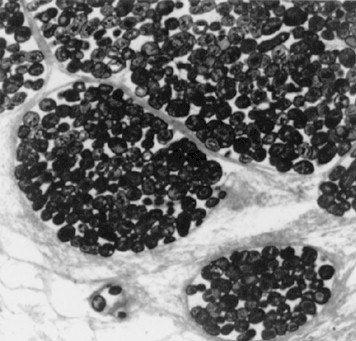

Embolismo séptico